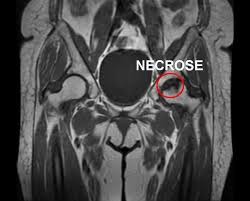

NECROSE ASSÉPTICA DO QUADRIL: UMA PREOCUPAÇÃO PARA PACIENTES REUMÁTICOS E COM HIV

Dores nos ossos que não apresentam alterações nas radiografias podem ser um indicador desta doença que atinge milhares de pessoas ...